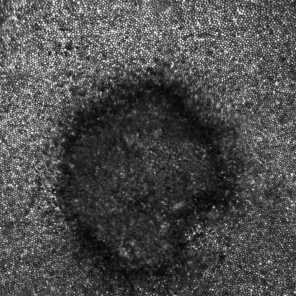

Payne's cells appeared to be damaged in the shape of the eclipse she witnessed. "We were able to see the crescent in New York City and that crescent was the exact pattern of damage," Deobhakta said.

"The suns rays … damage the layers that actually uptake the light to the brain," said Dr. Avnish Deobhakta, a retina surgeon at the New York Eye and Ear Infirmary of Mount Sinai, and author of a recent case study about Payne in JAMA Ophthalmology. "It's almost like (the blind spot) is branded in that retinal area."...